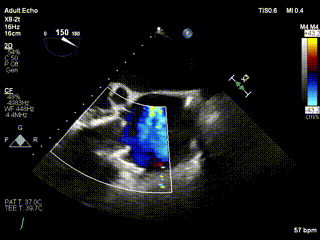

三例患者入院后,葛均波院士團隊周達新教授、潘文志教授、張源博士、陳莎莎博士及心超室的潘翠珍教授、李偉教授對患者的情況進行詳細評估和討論,最終決定為三例患者選擇LuX-Valve Plus40mm、50mm和50mm型號的瓣膜進行手術治療。手術后即刻拔除氣管插管,術后患者三尖瓣反流癥狀得到顯著改善,復查心超結果顯示人工三尖瓣瓣膜支架固定穩(wěn)定,瓣葉關閉形態(tài)未見異常,未見明顯反流。